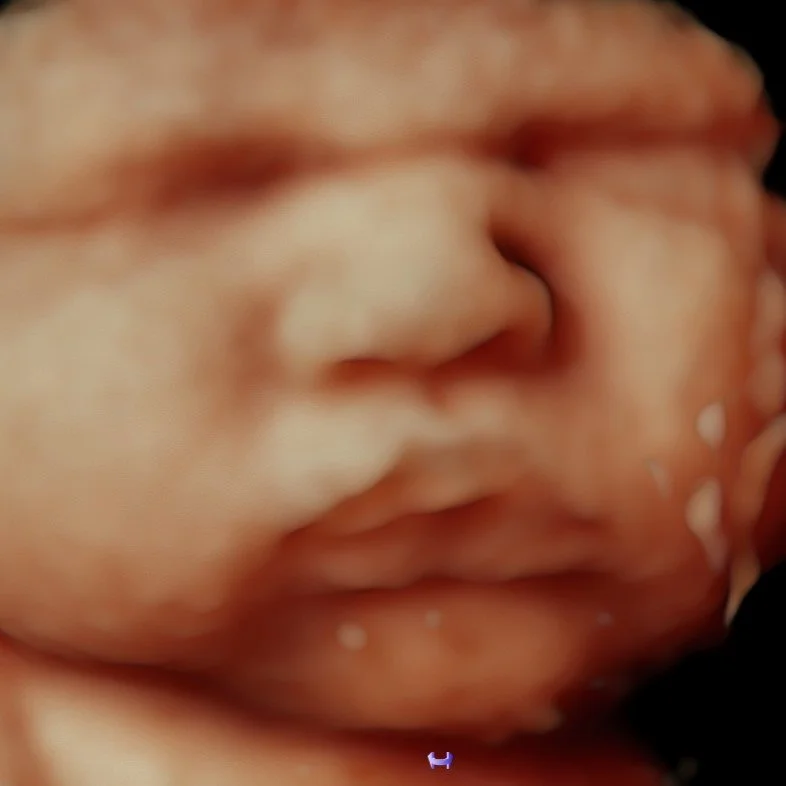

8K RealView — $39.99

Our most advanced image enhancement technology, transforming your baby’s ultrasound into a lifelike, high-definition portrait. Using cutting-edge software, we bring out incredible detail, depth, and realism so you can see your baby’s emerging features with stunning clarity and dimension. Delivered to your email within 1-2 business days of appointment.